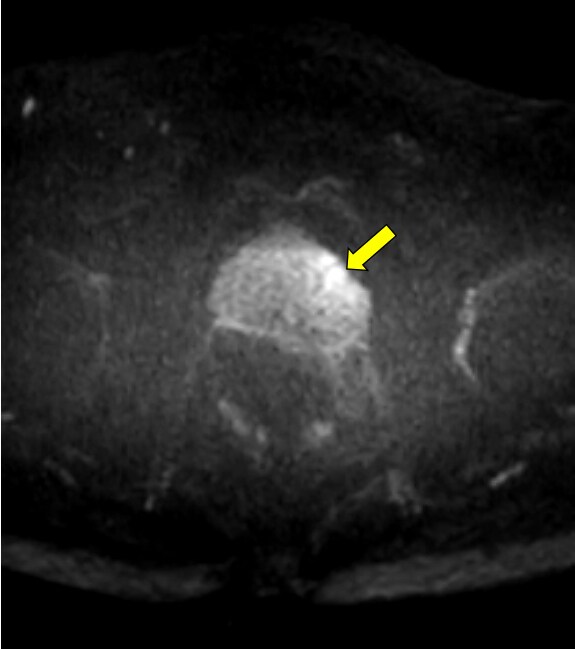

本症例ではPSA高値を契機に前立腺MRI検査を施行した。便秘症があるため、直腸は拡張し、内部にガスを含む便塊を認める。鎮痙薬は、既往症のため、使用せず、検査前の排便も不可能であったために、画質劣化が避けられない。腸管ガスによるひずみの影響で、全ての撮像シーケンスで、前立腺の後方の辺縁は不鮮明で、内部の信号が不均一となる。特に空気や蠕動の影響を受けやすい、拡散強調画像での画質劣化が著しい。

拡散強調画像(DWI)では、腸管ガスによるひずみの影響を減らすため、echo planar imaging(EPI)を用いたDWIよりTurbo spin echo(TSE)を用いたDWIを使用する。high b valueの画像は、computed DWIで作成することで、実際の撮像よりもノイズを低減できる場合がある。また、ダイナミック造影MRIを追加すると、短時間撮影のため前立腺の輪郭も明瞭で、癌部と非癌部のコントラストがつき、病変の検出に役立つ場合がある。